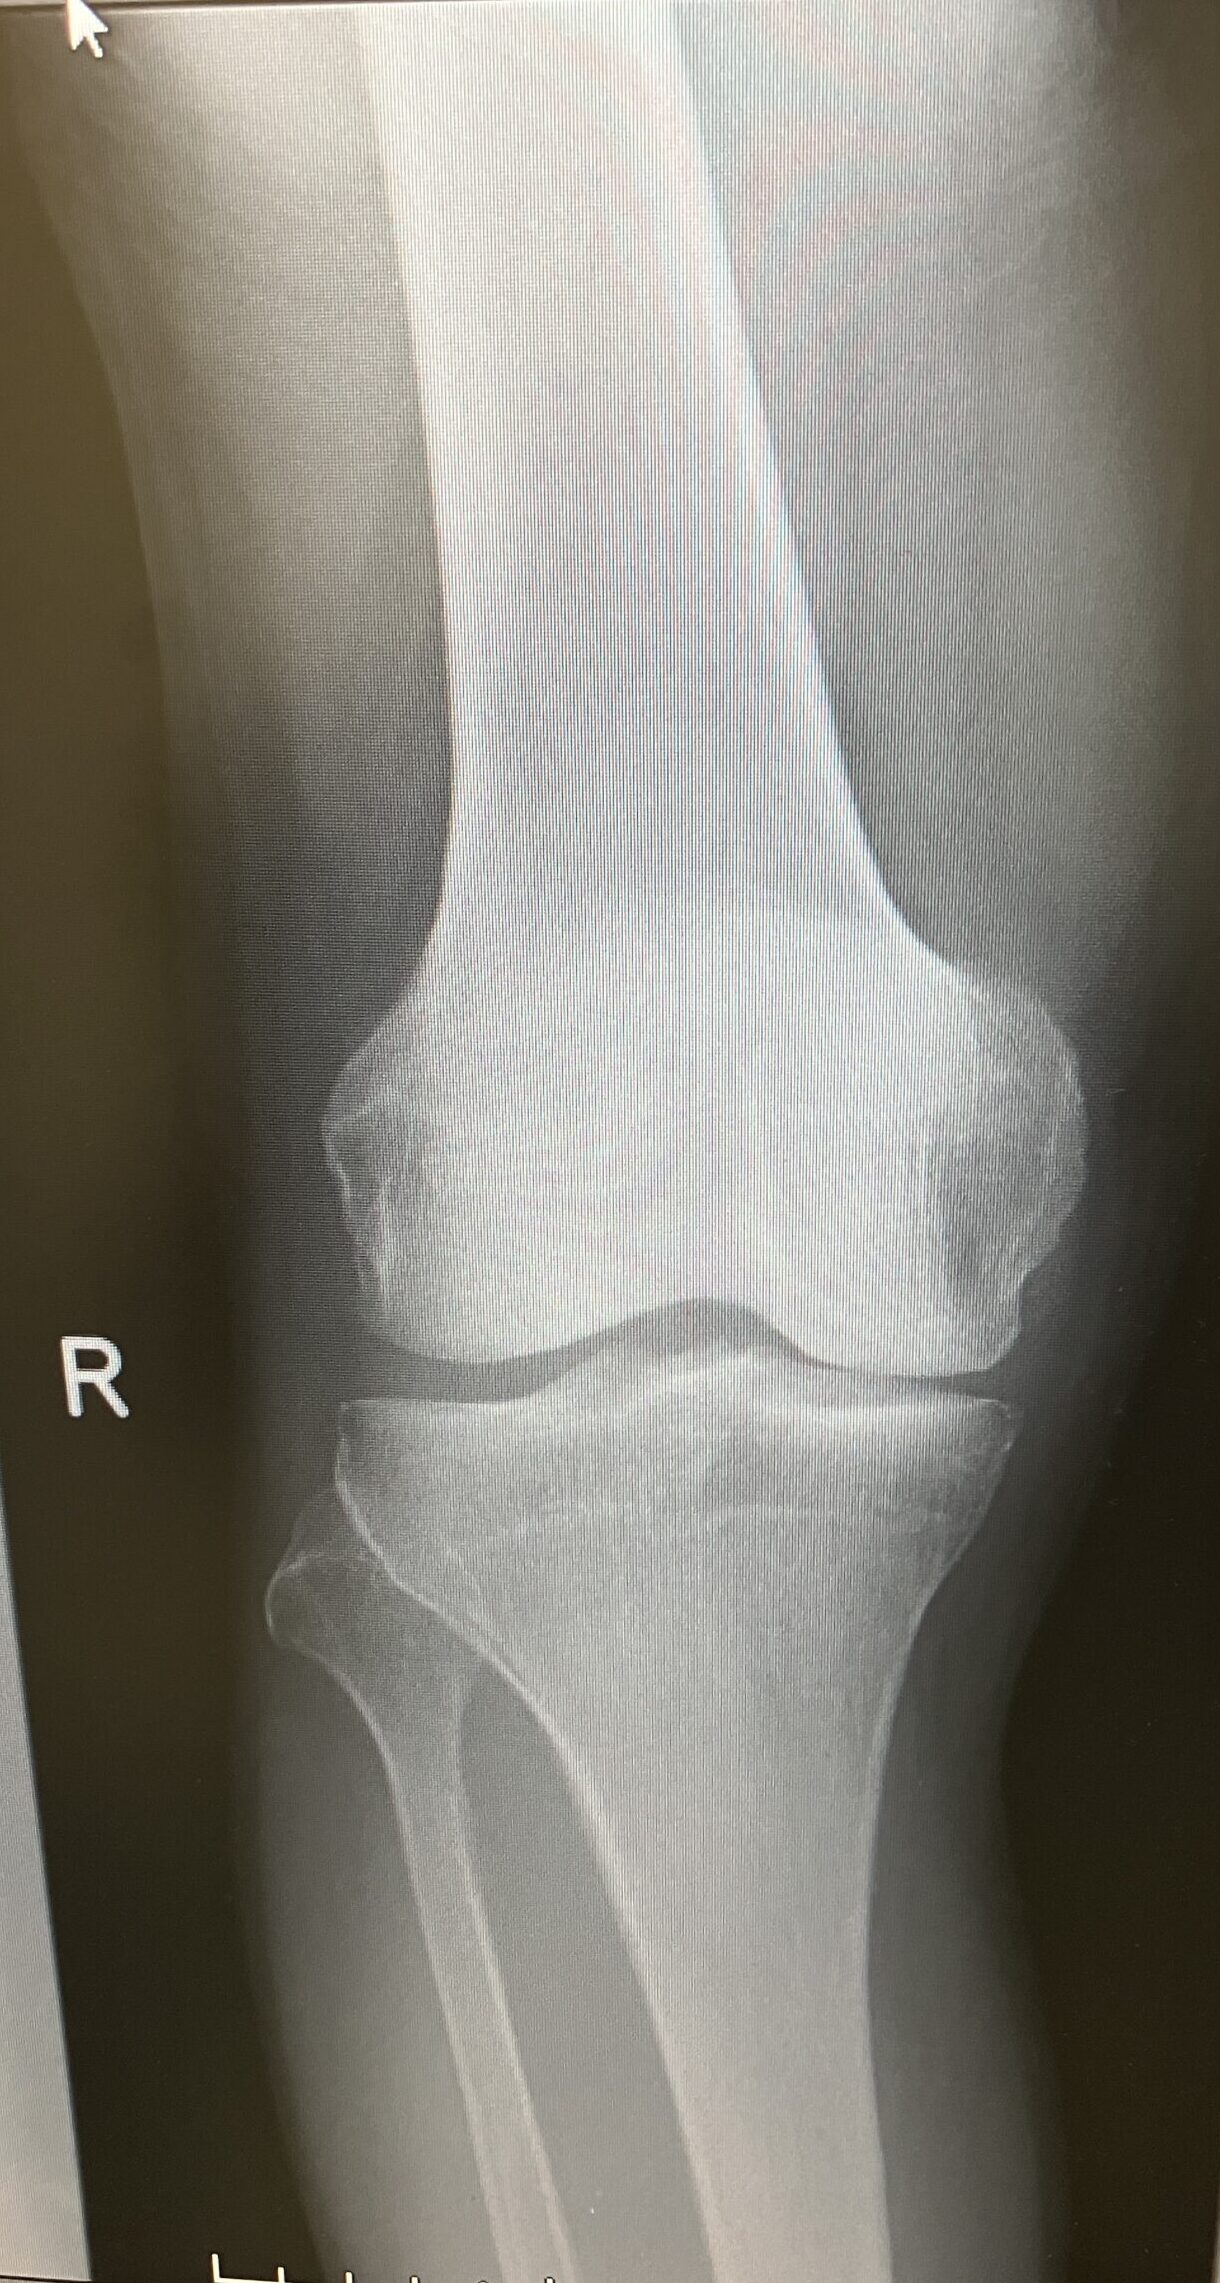

変形性膝関節症

IMG_0306